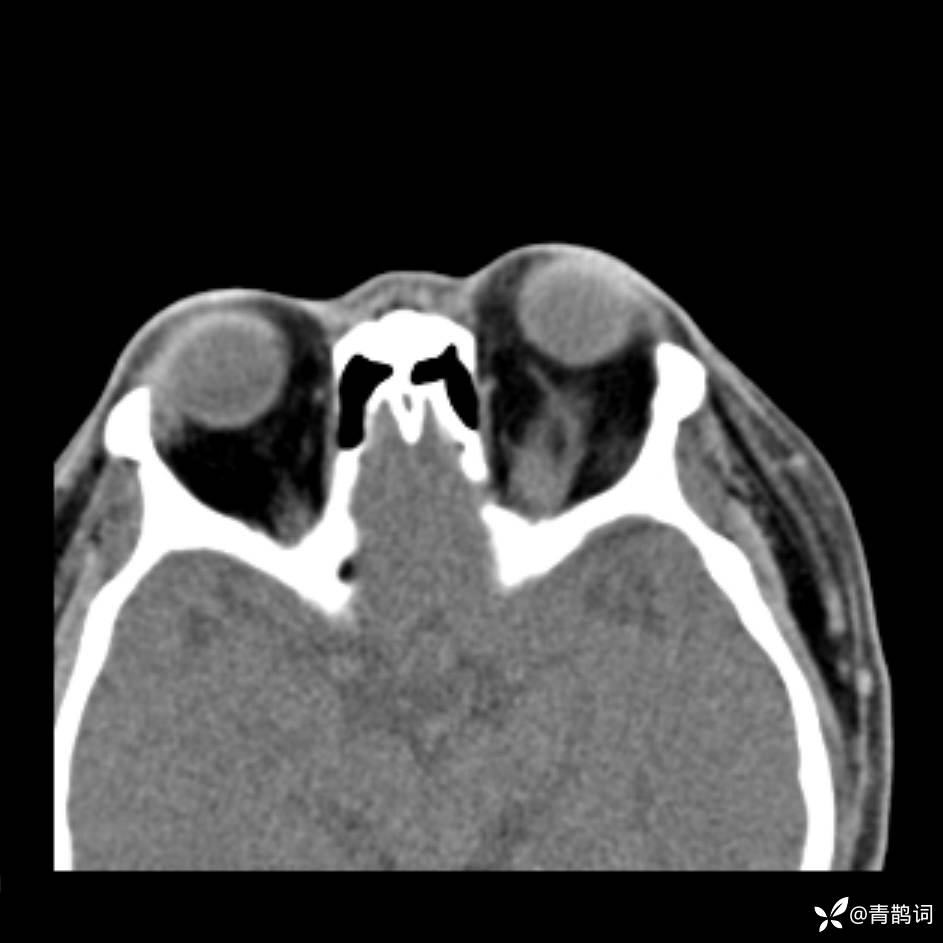

患者年龄:30岁。

患者性别:男。

简要病史:左颜面部肿胀2年,反复咳嗽咳痰,逐渐加重。

结合病史及影像学表现,期待评论区各位老师各抒己见~